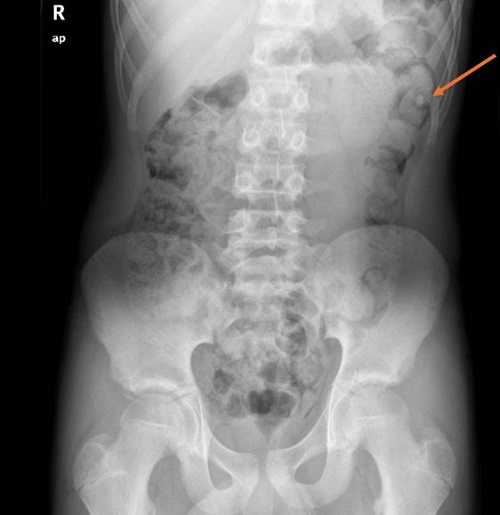

Adolescente de 15 años y medio de edad que acudió al Servicio de Urgencias por ingesta presuntamente accidental de un petardo. Tras la ingesta, refería presentar epigastralgia y náuseas, sin otros síntomas asociados. Análisis de sangre y electrocardiograma, ambos sin alteraciones. Se realizó radiografía de abdomen simple, donde se visualizó una imagen sugestiva de cuerpo extraño en cámara gástrica vs. duodeno proximal. Tras valoración quirúrgica, se decidió alta domiciliaria con control radiológico posterior, que se efectuó 72 horas después (Figura 1). En la misma, se objetivó la migración del petardo hacia el colon.

| Figura 1. Imagen radiodensa en ángulo esplénico del colon. Abundantes restos fecales. No dilatación de asas de ID que sugieran cuadro obstructivo |